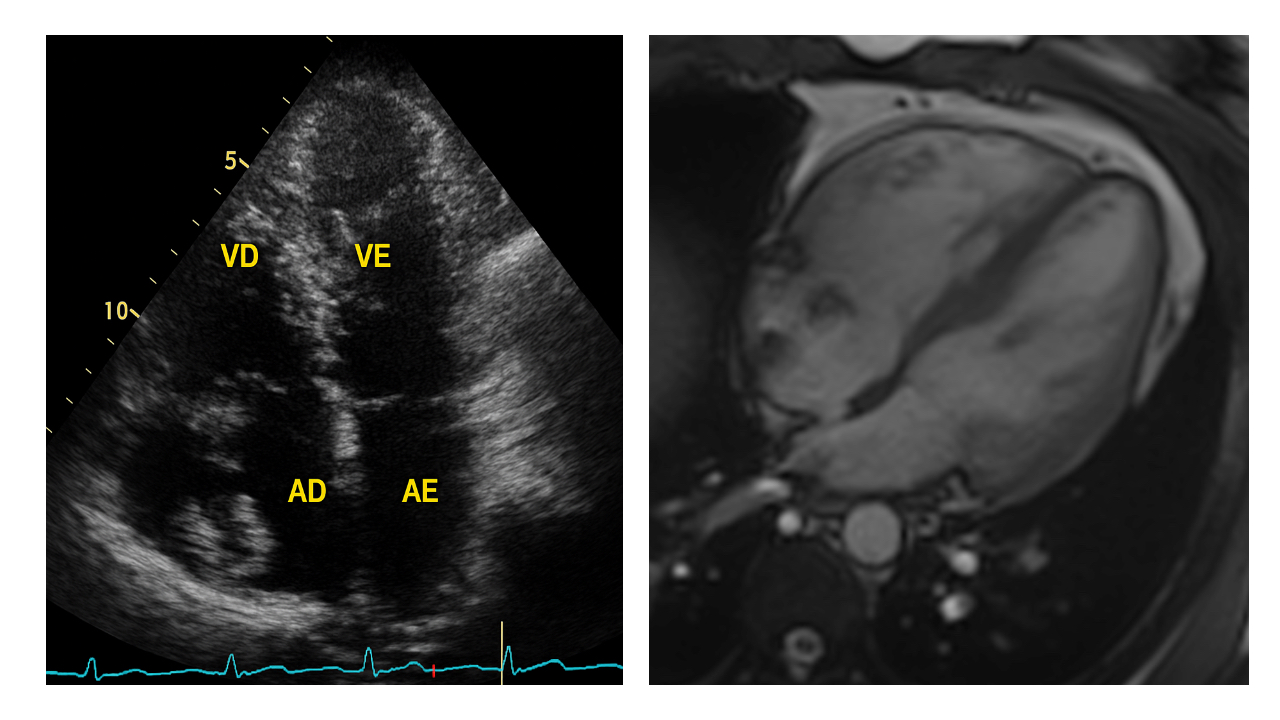

Image 3: Computed tomography. Left: 3D CTA reconstruction showing a stent in the left common iliac vein (white arrow), the embolized stent positioned within the RA with a fractured proximal edge and with its distal end lodged in the SVC (white arrowhead) and a small stent fragment located in the right pulmonary artery branch (yellow arrowhead). Upper right: View highlighting the relationship of the stent between the SVC and RA, with evidence of a fractured distal edge (blue arrowhead). Lower right: Axial view at the level of the pulmonary artery showing a metallic fragment in the right pulmonary artery branch (red arrowhead).